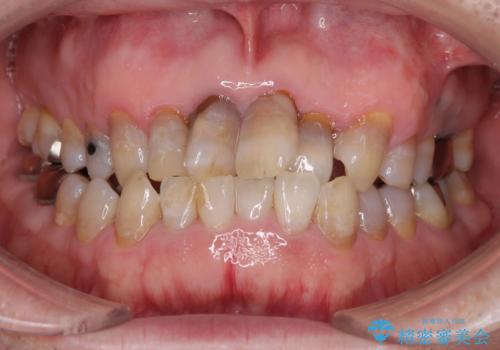

- 前歯の叢生と臼歯のクロスバイトを気にして来院された患者様です。

急速拡大装置による上顎の側方拡大を行い、その後はインビザラインより歯列を改善することとしました。

20代後半以降の男性は上顎骨の側方拡大処置の成功率が低く、今回も骨を拡大することができませんでした。

しかしながら、歯列を側方に拡大することができ、その後はインビザラインにて叢生を解消することができました。